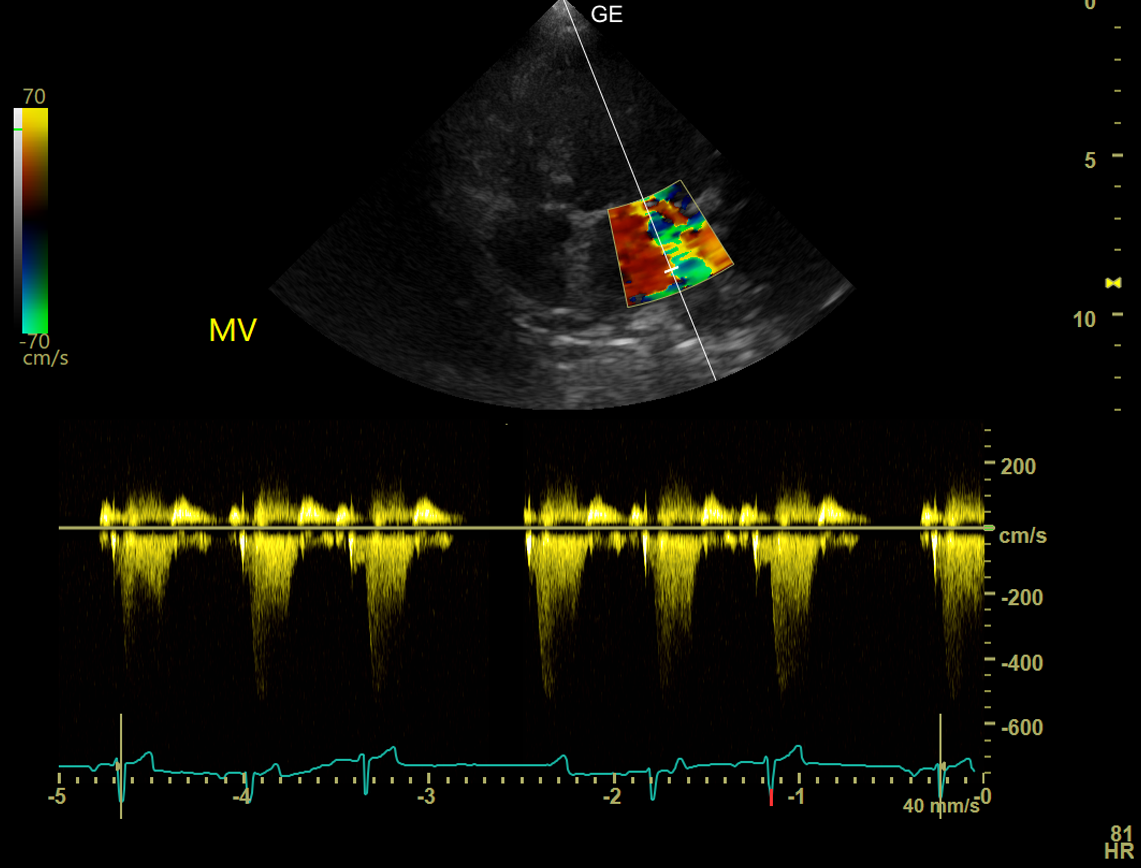

Leidet Ihr Tier an einer Herzerkrankung, kann diese mittels Auskultation (Abhören des Herzens) erkannt werden. Sind während der Auskultation des Herzens pathologische Geräusche des Herzens hörbar, empfiehlt sich eine Herzultraschalluntersuchung, die im Kleintierzentrum Landwasser routinemäßig durchgeführt wird. Dies ermöglicht eine genaue Diagnose des Herzleidens. Eine Sedierung des Tieres ist nicht notwendig und Sie können bei der Untersuchung selbstverständlich dabei sein. Wir haben mehrere Ultraschallköpfe zur Verfügung, um die kardiologische Untersuchung angepasst an die Größe Ihres Tiers durchzuführen. Mittels Farbdoppler können Blutströmungen in allen vier Herzkammern farblich dargestellt werden. Treten Undichtigkeiten der Herzklappen, pathologische Turbulenzen, Form- oder Größenveränderungen der Herzwand oder angeborene Herzdefekte auf, werden diese im Herzultraschall diagnostiziert und in ihrer Schwere klassifiziert, damit eine optimale Therapie gefunden werden kann.